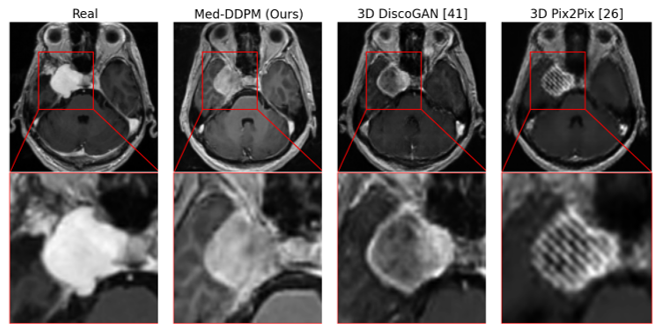

Fig.3 offers a closer look at tumor areas in axial plane images, comparing real and synthetic images from Med-DDPM and two other conditional GAN models. Fig.4 features synthetic images created using manipulated masks, which are generated by two different functions. The first function scales tumor masks from their center, while the second shifts them within the brain in axial, coronal, and sagittal planes. Fig. 5 demonstrates the variety of synthetic images produced from a single input mask. The Pix2Pix model often yields blurry images, especially with unseen test masks. DiscoGAN performs better, producing more realistic images with distinct tumor areas. However, DiscoGAN’s images lack clear brain features and exhibit coarse gyri and sulci.

In contrast, our Med-DDPM model excels in generating highly realistic and detailed images. It captures both brain features and tumor regions clearly, though occasionally it shows incomplete tumor ring enhancement, similar to real images. The peri-tumoral edema rendered by Med-DDPM appears more realistic than the isotropic low-intensity output of DiscoGAN, making these synthesized images closely resemble real ones.

Regular visual assessment tests were conducted throughout the experimentation phase. The experts were presented with a mixture of real and synthetic 3D images generated by the proposed model and the two baseline models. The experts evaluated the quality of the generated images. It was evident to the experts that the synthetic images produced by the two baseline models exhibited blurriness and lacked realistic-looking brain features. In contrast, the synthetic images generated by our proposed method appeared more realistic. However, upon careful examination of the axial plane, the experts were able to identify the synthetic images due to slight inconsistencies in vessel continuity within the Circle of Willis area. Additionally, the synthetic images did not exhibit the presence of mass effects around large tumors, which typically result in shifts in the ventricles and the midline.